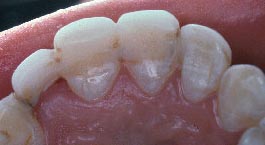

Este paciente se presentó con la queja principal de incomodidad en el funcionamiento de los dientes anteriores inferiores. Nótese la pérdida y recesión de encía.

La evidencia clínica de una enfermedad periodontal grave fue respaldada por las pruebas radiográficas en las que se observa una pérdida de hueso de más del 70% en los incisivos mandibulares y la presencia de un grado de movilidad 2 para los cuatro incisivos.

La queja principal de este paciente era la incomodidad durante el funcionamiento de los dientes anteriores inferiores. Nótese la pérdida y recesión de encía. Todos los incisivos tenían grado 2 de movilidad.

Otro factor que complicaba el caso fue que el paciente había completado dos años de tratamiento de ortodoncia para cerrar el espacio que existía en anteriores debido a la pérdida de un incisivo central por enfermedad periodontal. Hay evidencia radiográfica de pérdida de masa ósea de más del 70% en el incisivo central restante.